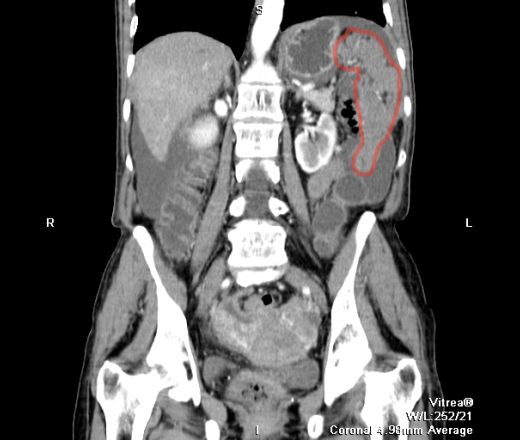

Канцероматоз таза

Канцероматоз таза 112 фото